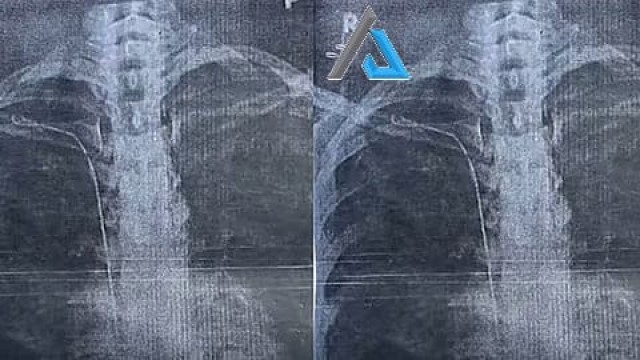

ആരോഗ്യ പ്രശ്നം ഉണ്ടായപ്പോൾ ഇതേ ഡോക്റ്റർക്ക് കീഴിൽ രണ്ടു വർഷം ചികിത്സ തുടർന്നു. ആരോഗ്യപ്രശ്നം കടുത്തപ്പോൾ മറ്റൊരു ആശുപത്രിയിൽ ചികിത്സ തേടി. എക്സ്റേയിലാണ് നെഞ്ചിനകത്ത് ട്യൂബ് കണ്ടത്. വീണ്ടും സന്ദർശിച്ചപ്പോൾ ഡോക്റ്റർ പിഴവ് സമ്മതിച്ചെന്ന് യുവതി പറഞ്ഞു. മറ്റു ഡോക്റ്റർമാരുമായി സംസാരിച്ച രാജീവ് കുമാർ കീ ഹോൾ സർജറിയിലൂടെ ട്യൂബ് പുറത്തെടുക്കാമെന്ന് യുവതിയെ അറിയിക്കുകയും ചെയ്തു.

സംഭവം രഹസ്യമാക്കിവയ്ക്കണമെന്ന് ഡോക്റ്റർ ആവശ്യപ്പെട്ടതായും യുവതി വെളിപ്പെടുത്തി. പിന്നീട് രാജീവ് കുമാറിന്റെ നിർദേശപ്രകാരം ശ്രീചിത്ര ആശുപത്രിയിൽ ചികിത്സ തേടി. രക്തക്കുഴലുമായി ട്യൂബ് ഒട്ടിച്ചേർന്നെന്ന് സിടി സ്കാനിൽ വ്യക്തമായി.